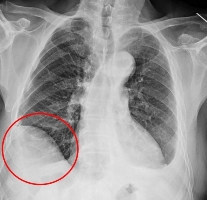

75歲吳先生因肝臟細胞癌在仁愛長庚合作聯盟醫院(大里仁愛醫院)接受治療,期間發現右下肺有一顆約1.2公分新發現的腫瘤,因疑似肺癌故轉介到胸腔及心臟血管外科廖啟耀主任門診,經醫療團隊和家屬討論後決定做手術切除該腫瘤。由於病人過去有車禍導致橫隔膜受傷的病史,所以讓手術預期難度相對提高,經採用達文西機器人手術系統執行肺節切除手術,並且順利地於術後第三天出院返家休養。

廖啟耀主任表示,雖然肺臟腫瘤手術在台灣十分普及且發達,但是有些病人的情況會使醫師預期手術難度提高,其中以過去有過外傷經歷、曾經接受過胸腔手術、肺臟腫瘤接受過放射性治療的病人最為常見,這類病人常見的手術困難度為解剖構造的改變,常因為胸腔發炎反應的影響,讓肺臟與周遭肋膜產生沾黏,同時血管的方向也更難分辨,對執行手術醫師而言是一項困難的挑戰。